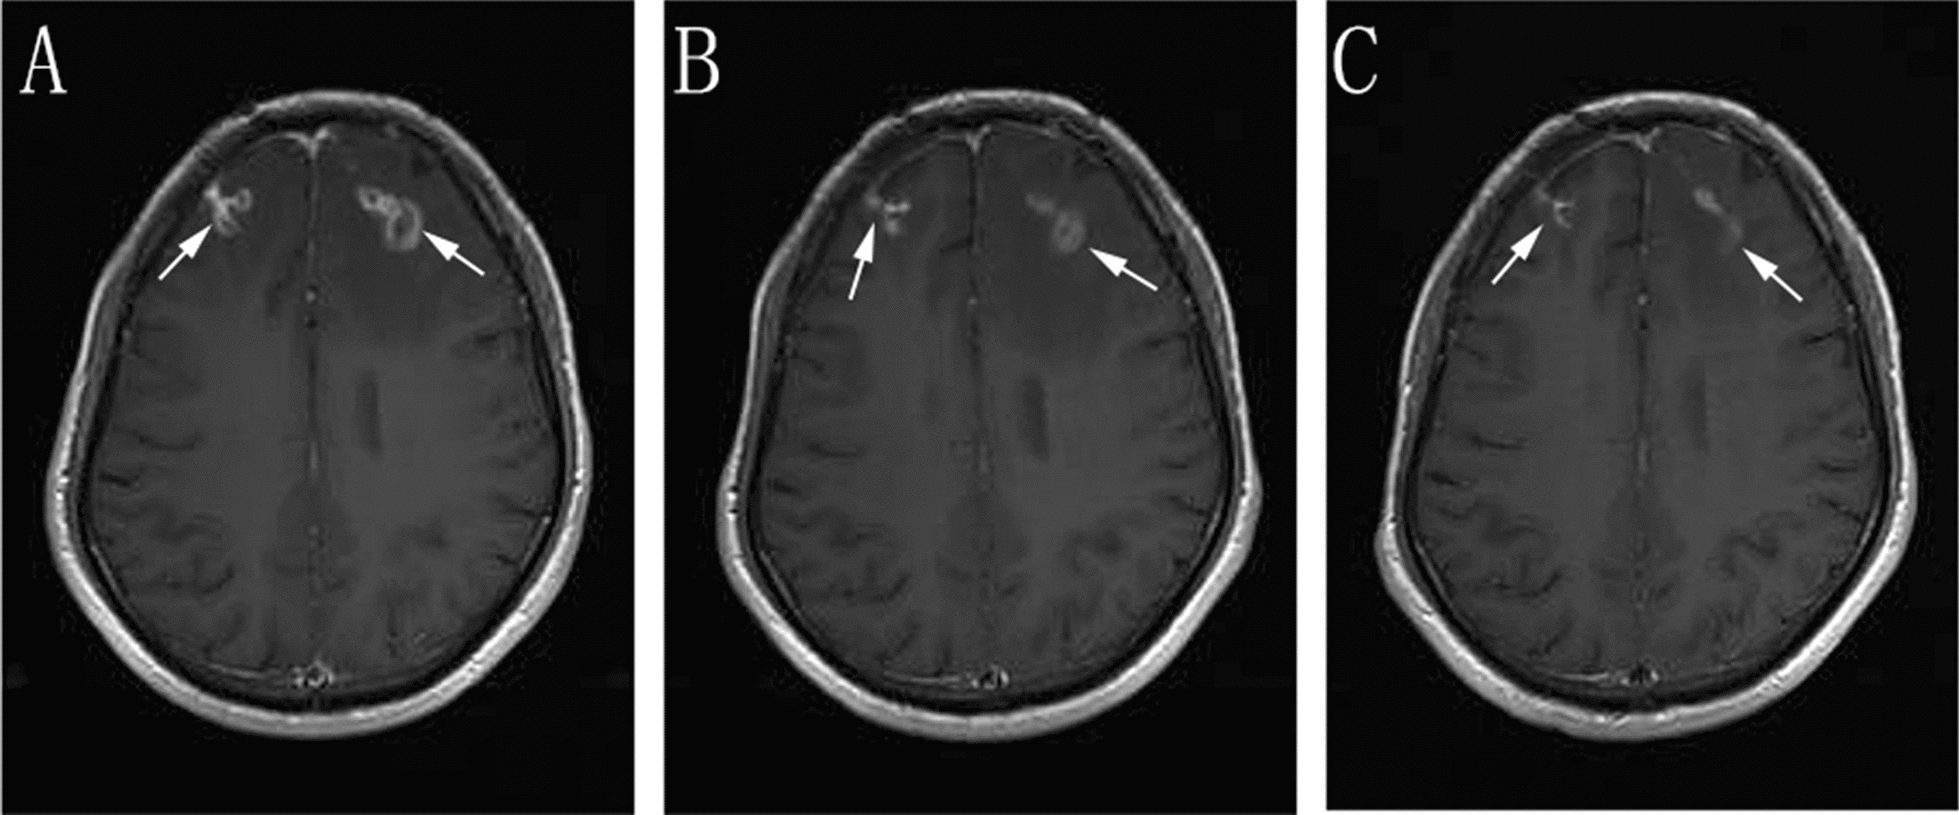

In addition, the BALF-GM test result was positive. Based on the patient’s symptoms, signs, laboratory tests, and past treatment reactions, the diagnosis was corrected to CNSAG, invasive pulmonary aspergillosis (IPA), and AIDS. Voriconazole (intravenous drips of 6 mg/kg/day q12-h on the first day, followed by intravenous drip of 4 mg/kg/day q12-h) was administered for antifungal treatment. Due to the interaction between voriconazole and EFV, the antiviral treatment regimen was revised to 3TC, TDF, and dolutegravir (DTG). After 2 weeks of this treatment, the patient’s ghosting vision and facial anhidrosis were relieved. The routine examination of cerebrospinal fluid revealed normal biochemistry. His cranial MRI indicated that the lesions in the frontal lobe were absorbed, and the surrounding edema was alleviated (Fig. 2). The patient was discharged and continued on oral voriconazole treatment (200 mg/kg/day). After 6 weeks of antifungal treatment, the patient's ghosting vision and facial anhidrosis were significantly relieved. Re-examination of his cranial MRI indicated that the lesions in the frontal lobe were significantly absorbed and improved, and the surrounding edema was alleviated (Fig. 2). His chest CT showed focal absorption (Fig. 3).

Fig. 2.

Enhanced scanning of cranial MRI A before treatment: multiple intracranial circular and small-nodular enhanced lesions, as indicated by the arrow, B two weeks after treatment C six weeks after treatment, B and C indicate that the intracranial lesions were absorbed and improved compared with those before treatment